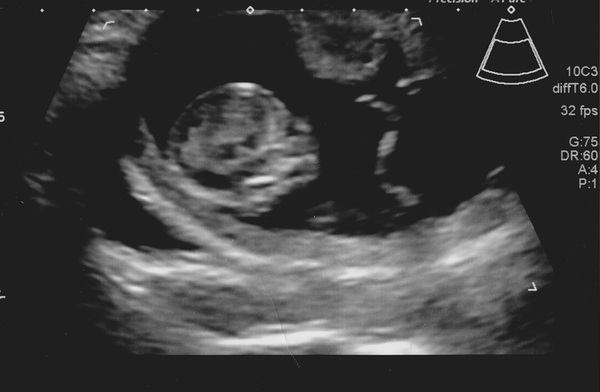

RhiPea · 03/08/2015 15:28

So turns out I've just been a very lucky girl with no symptoms! Here is my little tad (has it's dad's long legs by the looks of things!) Had a little wriggle & wave then had a stretch and turned over!